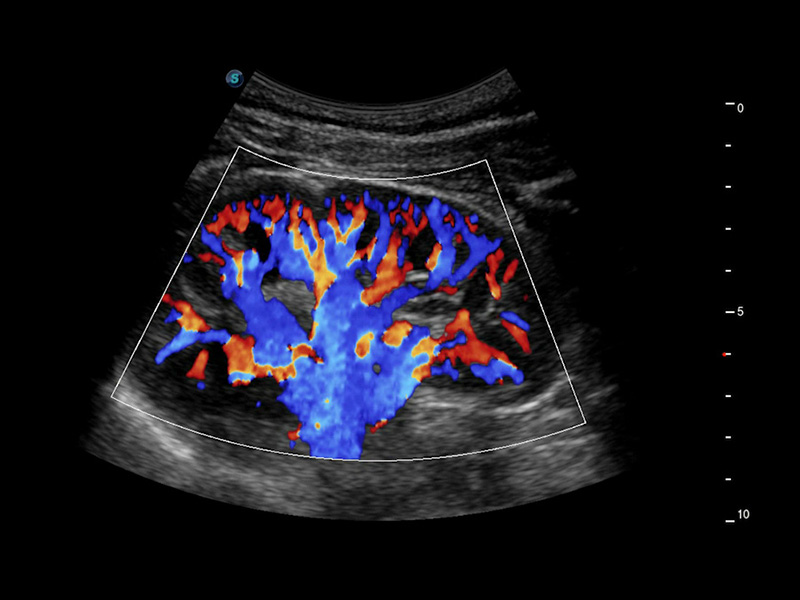

CEUS

Sfrutta il pieno potenziale dell'imaging a micro flusso

Il pacchetto completo di imaging ecografico e quantificazione con mezzo di contrasto di P60 offre ai medici una soluzione completa per valutare le dinamiche di perfusione in un'ampia gamma di ambiti clinici.

• Nodulo tiroideo maligno con CEUS

• Colestasi ostruttiva con MFI

• HCC con modalità mista

• HCC con MFI-Time

• CEUS con curva TIC

Micro F

Consente la visualizzazione delle strutture microvascolarizzate

Micro F offre un metodo innovativo per ampliare la portata di flusso visibile nell'ecografia, in particolare per visualizzare l'emodinamica dei piccoli vasi a flusso lento. Grazie all'adozione di un filtro adattivo avanzato e all'accumulo di segnali temporali e spaziali, Micro F è in grado di distinguere in modo efficace il flusso minuto dal movimento di tessuto sovrapposto e di rappresentare l'emodinamica con sensibilità e risoluzione spaziale più elevate.